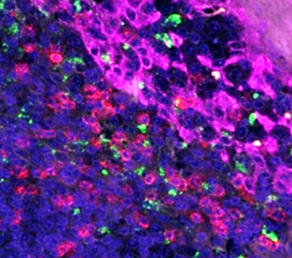

Multiplexing

Detecting multiple biomarkers in one sample maximizes data acquisition but complicates the workflow.

To simplify the multiplexing process, they offer products like VectaPlex™ Antibody Removal Kits to eliminate cross-linking over multiple rounds of staining,

secondary antibodies in a variety of species for exceptional specificity and sensitivity across diverse research needs, and more.